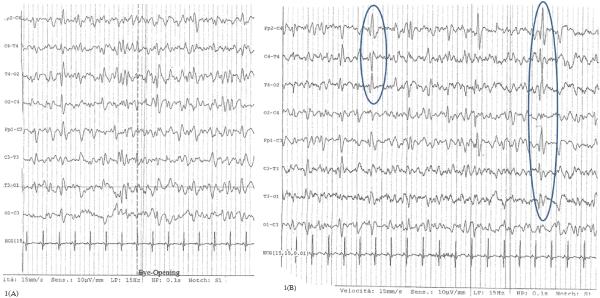

The day after, as the patient was still in coma with sporadic break in the spontaneous ventilation, a liquor puncture was done and both chemo-physical and infective (regarding Herpes Human Virus 1- 2, Varicella-Zoster Virus, Enterovirus and Citomegalovirus) liquor exams were negative, so an infectious encephalopathy was excluded. Electroencephalogram (EEG) showed electric anomalies on frontal-temporal-central regions of right side with contra-lateral diffusion in a diffuse slowing tracing, not responsive to eye opening (Figure 1A and 1B).

Figure 1. EEG during acute encephalopathy: slowing tracing characterized by theta and delta waves A: trace not responsive to eye-opening, B: anomalies on frontal-temporal-central regions of right side with contra-lateral diffusion